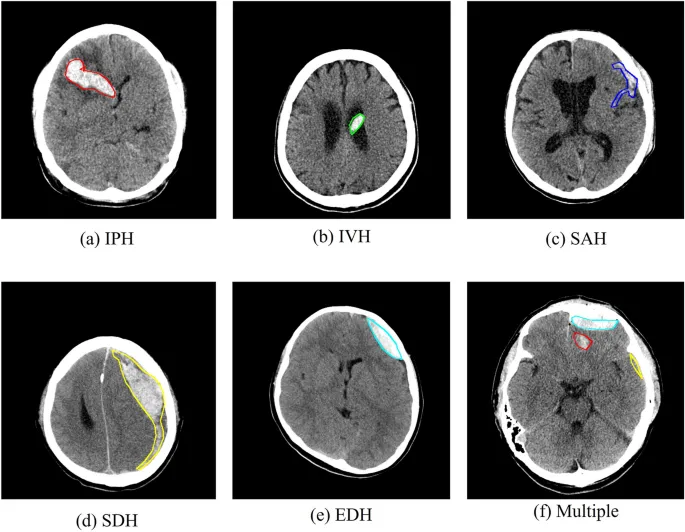

Intracerebral Hemorrhage (ICH)

- CT Finding: Blood within the brain parenchyma.

Subarachnoid Hemorrhage (SAH)

- CT Finding: Blood in cisterns and sulci.